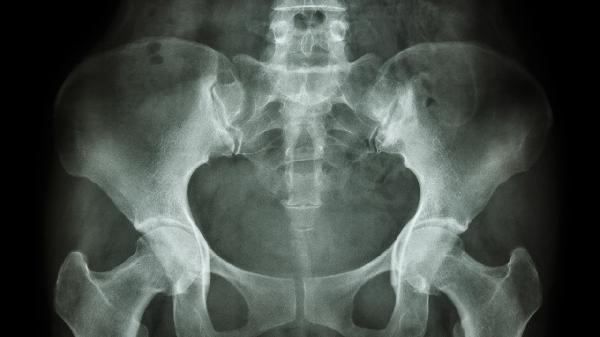

分娩过程中可能发生耻骨联合过度分离,表现为局部压痛、下肢活动受限,严重时出现步态异常。该情况需通过骨盆X线或超声确诊,轻度分离可通过卧床休息、骨盆束缚带固定恢复,疼痛明显者可短期使用洛索洛芬钠片消炎镇痛。若分离超过10毫米且保守治疗无效,可能需要手术复位固定。

跌倒、撞击等外力作用可能导致耻骨骨折或软组织挫伤,常伴随局部淤血肿胀、触碰痛等症状。急性期需冰敷并限制活动,骨折患者需使用骨盆兜带制动,可配合塞来昔布胶囊缓解疼痛。严重移位性骨折需手术内固定,术后需进行渐进式康复训练恢复骨盆稳定性。